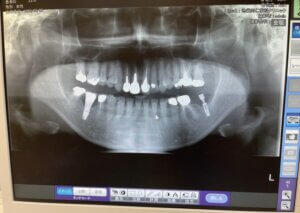

>>レントゲン検査(18枚法)

一本一本の歯を診査するためにレントゲンをお撮りします。

歯の周りの骨・かぶせ物・虫歯・根の病気をチェックします。